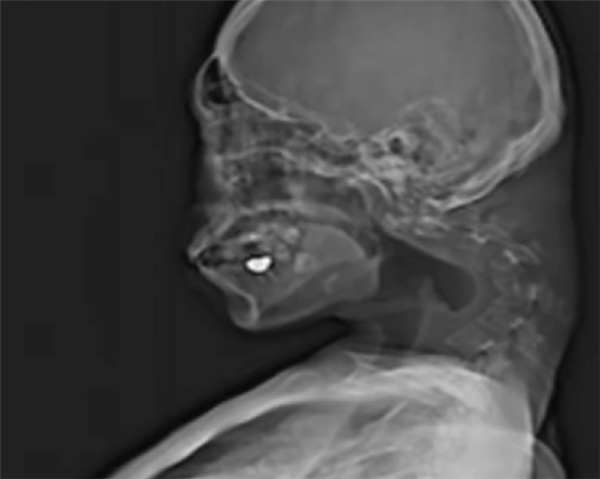

一名25岁男性患者因长期保持低头姿势玩手机游戏,导致颈部椎骨严重变形,在颈椎处形成了一个明显的异常包块。医学检查显示,其颈椎因长期处于不自然位置而出现"极度伸展"的病理改变。

为治疗这一罕见病症,医疗团队实施了多阶段外科手术:首先切除病变的椎骨部分及颈部形成的疤痕组织,随后通过植入螺钉和金属棒进行颈椎固定与矫正。目前,患者已能自如保持头部水平位置,一年后复查时抬头功能和吞咽障碍均未复发。